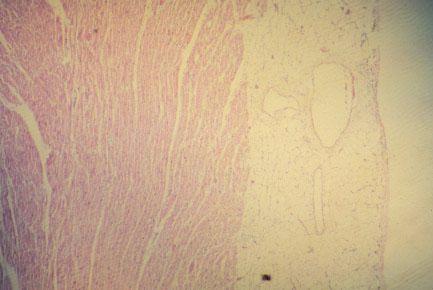

VI-2 (3) Slide 31, Heart (H&E). Low power view of epicardium (right) and myocardium (left). Observe large vessels and adipose tissue in epicardium which is lined by mesothelial cells.